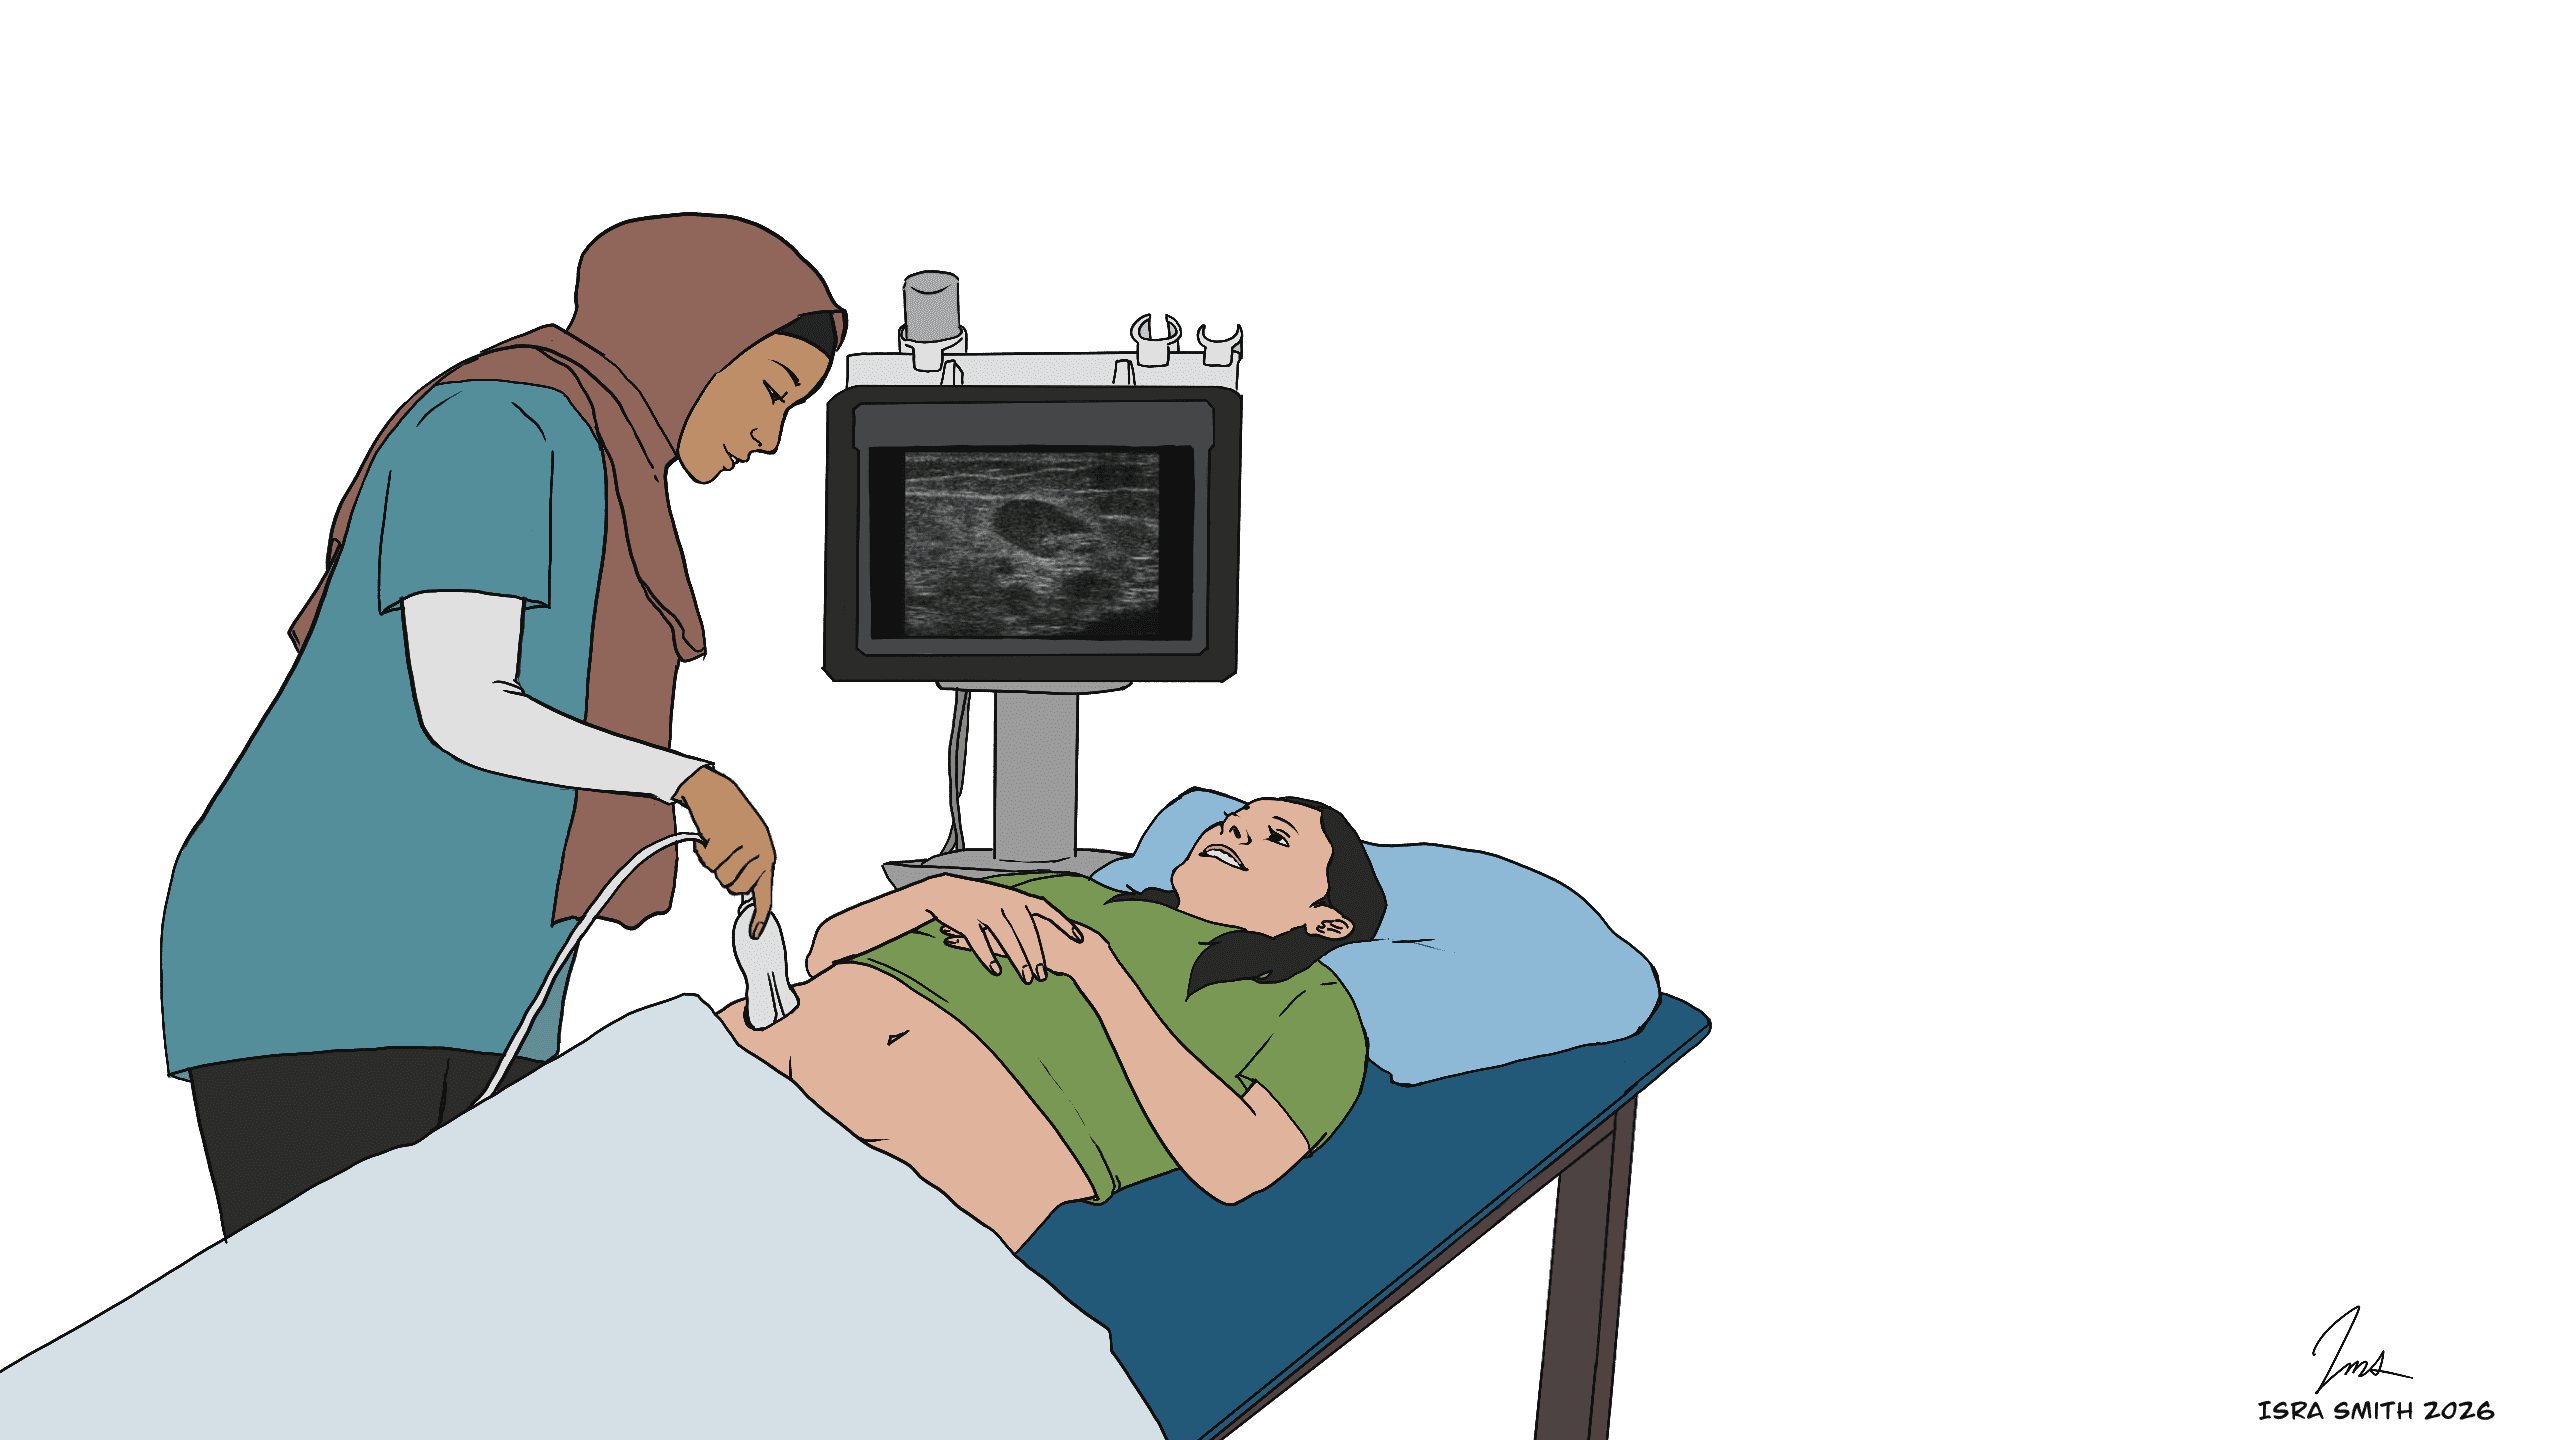

These images illustrate how ultrasound is used during ILIT to locate superficial lymph nodes and guide accurate allergen delivery during treatment.

Yes. ILIT uses low doses of allergen extract, and real-time ultrasound guidance ensures precise placement inside the lymph node. Most patients experience only mild, temporary soreness at the injection site.